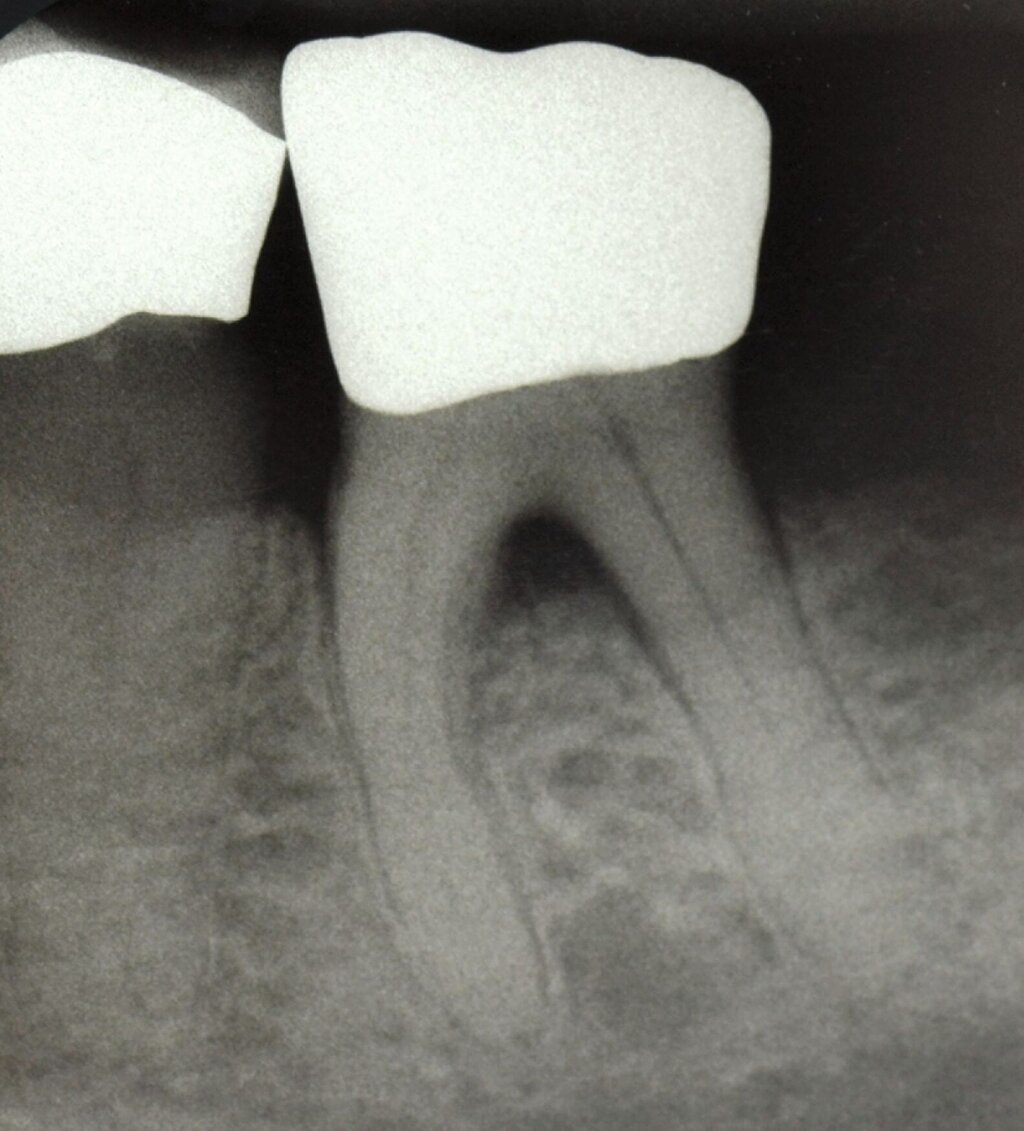

Da der histologische Nachweis einer erfolgreichen Furkationsregeneration kein praktikabler Endpunkt für kontrollierte klinische Studien ist, dienen Veränderungen bei direkten Knochenmessungen (offene Messungen: horizontales Knochensondierungsniveau bei der Operation und während eines „Re-entry“-Eingriffs) als primäre Ergebnisvariablen zur Bewertung des klinischen Erfolgs, während geschlossene Messungen wie der klinische Attachmentgewinn (horizontales/vertikales Attachmentniveau (CAL)), die Reduktion der Taschensondierungstiefe (TST) und röntgenologische Beurteilungen als sekundäre Zielparameter dienen können [Machtei, 1997]. Zu den von den Patienten berichteten Ergebnissen nach einer regenerativen Furkationschirurgie können postoperative Schmerzen, die Komplikationsrate, der wahrgenommene Nutzen und die Veränderung der Lebensqualität gehören.

Fall 2 – fortgeschritten